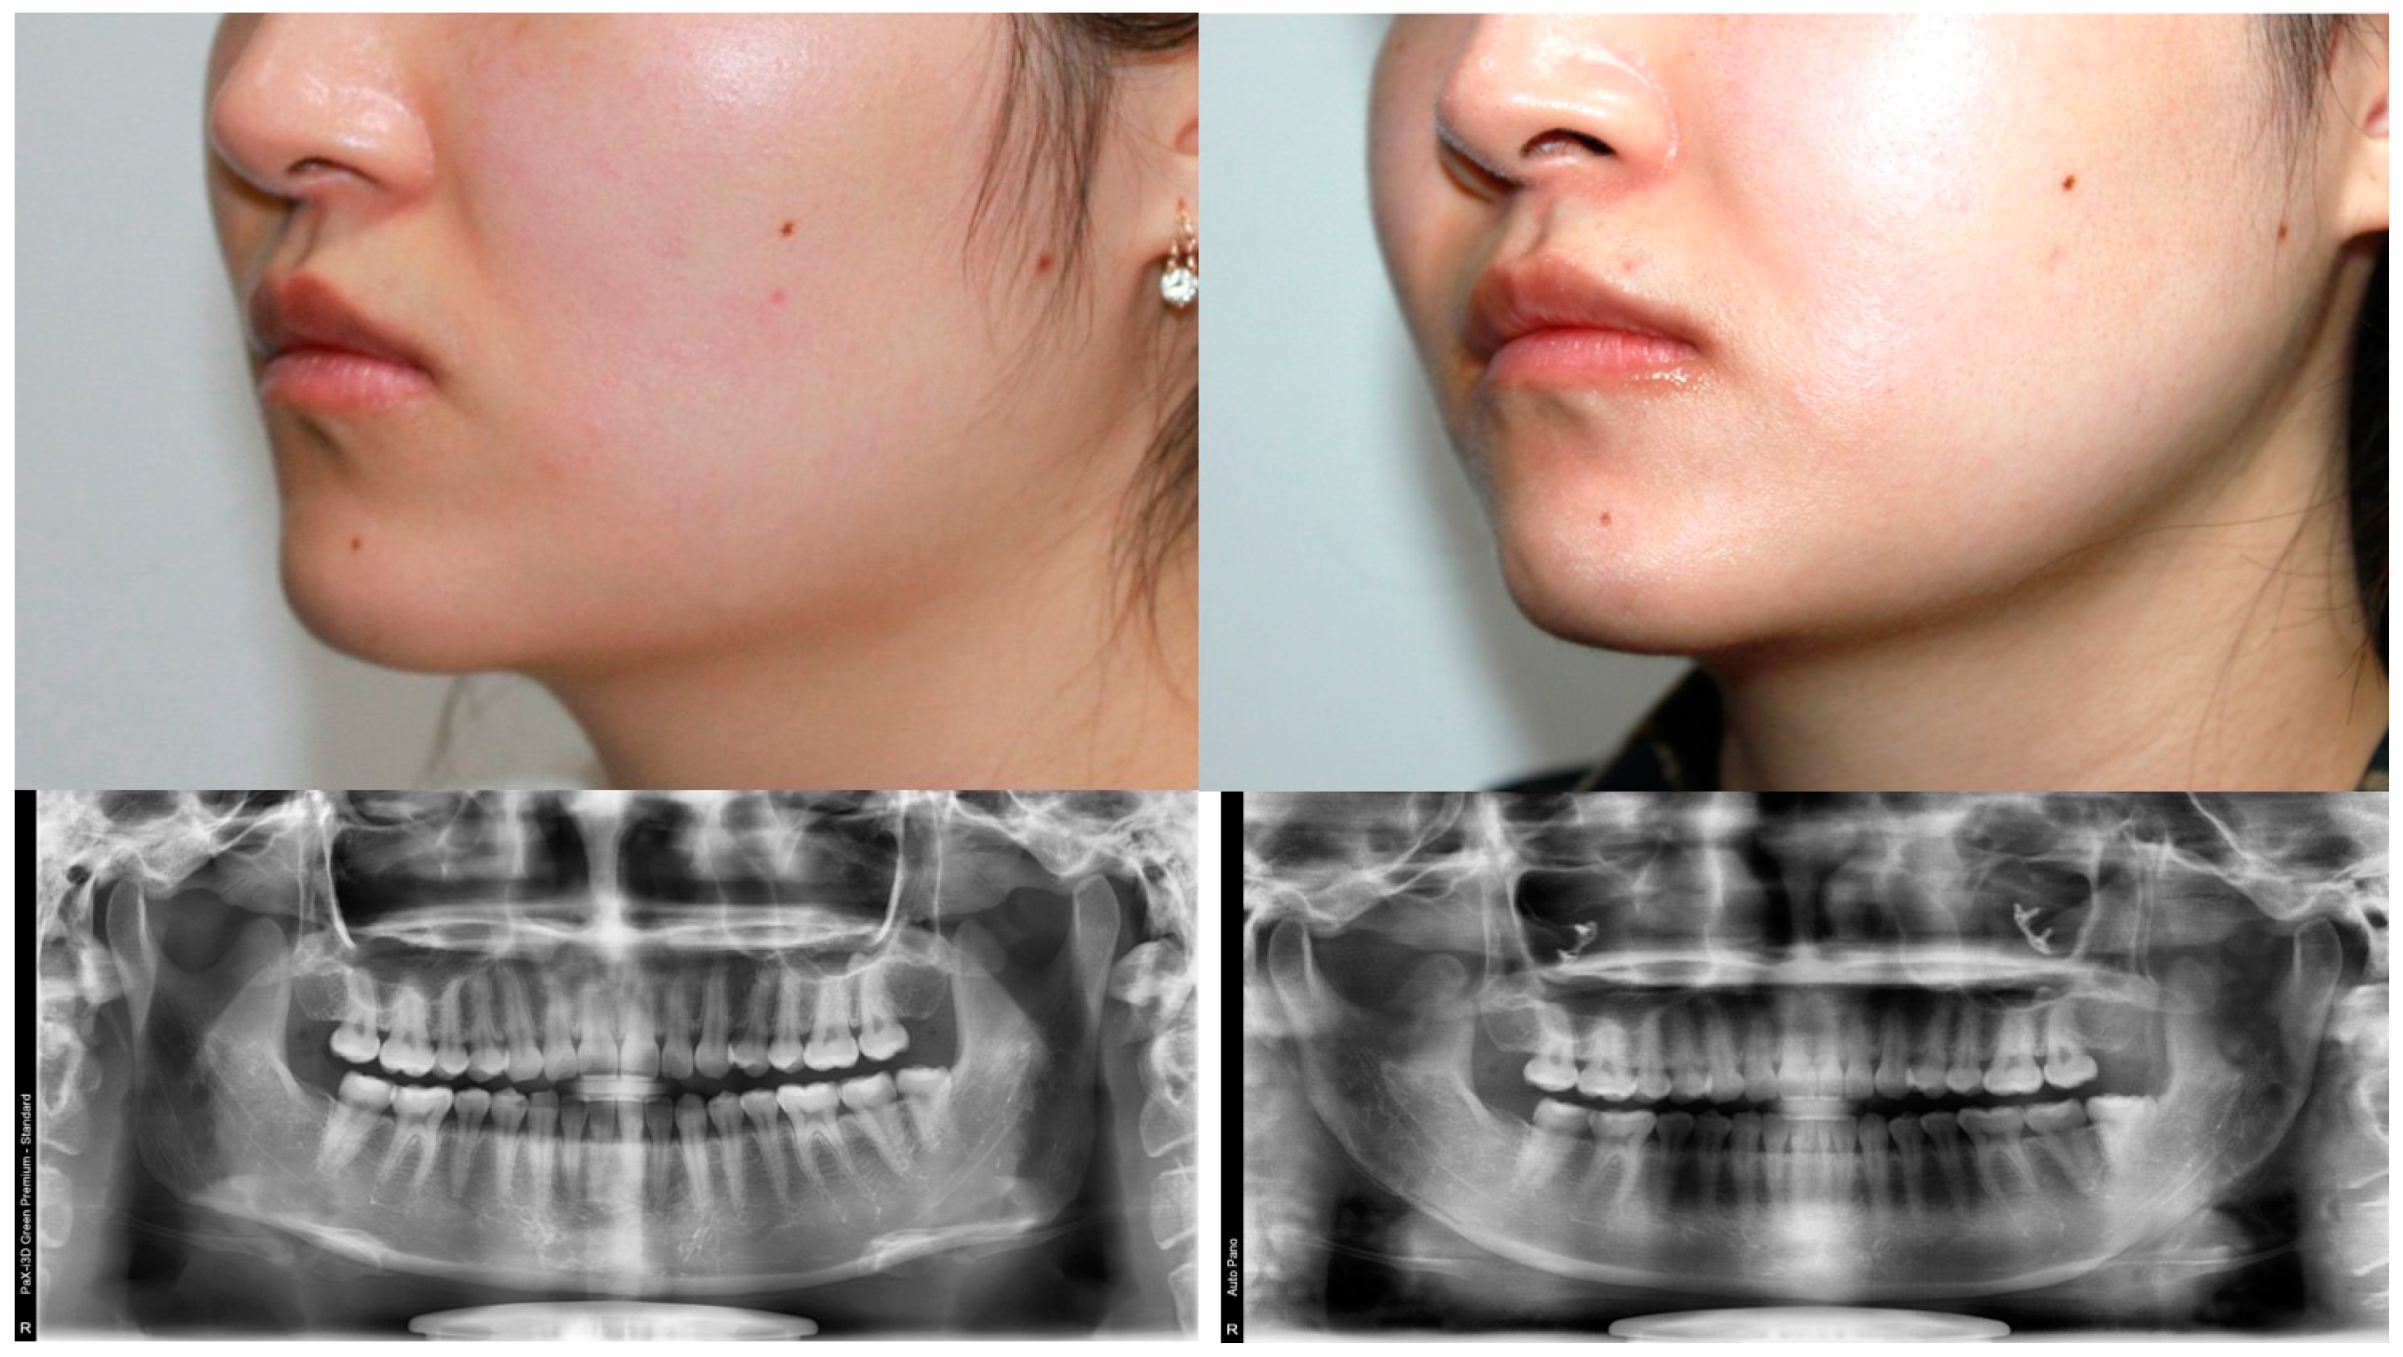

3. Results